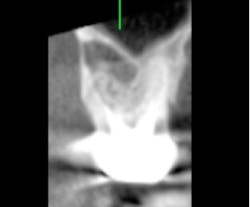

As my implant experience grows, I find myself ordering CBCT-based surgical guides more often. When used properly, a guide can make the procedure shorter, safer, and less stressful for both the doctor and the patient. I am a firm believer in placing screw-retained restorations whenever possible; preplanning my surgery with a digital wax-up and using a surgical guide ensures that the implant is in the optimum restorative position (figures 4–5). Even though an experienced surgeon with top-notch clinical skills can place an implant in an acceptable position most of the time, there is no way they can place it in a better position than with a surgical guide. They can only hope to do as well—not better.